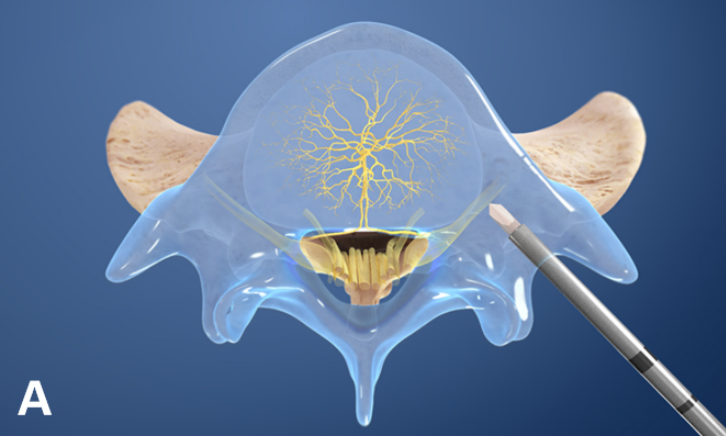

椎间盘由纤维环、髓核及透明软骨终板组成,其中软骨终板即椎体的上下软骨面,形成髓核的上下界,与相邻的椎体分开;纤维环是在上下软骨板的周围有一圈同心层排列的纤维组织;髓核是一种富有弹性的半流体的胶状物质,占椎间盘横切面的 50%~60%。

软骨终板在椎体上下各有 1 个,其平均厚度为 1 mm。组织学上为薄的透明软骨,它的作用是承受压力,保护椎体,控制椎间盘营养渗透,只要软骨终板保持完整,椎体一般不会因压力而产生骨质吸收现象。

其实,椎体及终板的神经支配主要来自于窦椎神经的分支椎基神经,而椎基神经中 P 物质和 PGP 9.5 呈阳性反应,提示椎基神经可传递疼痛。生理情况下,终板的神经密度类似于外层纤维环。

然而,病变终板的神经密度明显高于无病变终板和病变的纤维环。

左图为正常的纤维环和终板神经支配情况,右图为病变的纤维环和终板,可见神经末梢向深层长入。

理论上讲,任何接受神经支配的腰椎及其相邻的软组织结构都可能是腰痛的起源部位。因此,Modic 改变有引起腰痛的解剖学基础。